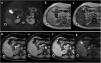

The use of hepatobiliary-specific contrast agents in liver MRI is a crucial diagnostic tool for evaluating liver disease, enabling the detection and characterisation of focal lesions and vascular alterations, as well as the assessment and grading of chronic hepatopathy. Paramagnetic hepatobiliary-specific contrast agents are gadolinium-based, partially taken up by hepatocytes, and excreted via both renal and biliary pathways. There are two linear ionic molecules that are currently commercially available: gadobenic acid (Gd-BOPTA) and gadoxetic acid (Gd-EOB-DTPA). Their main clinical indications include distinguishing and characterising focal liver lesions on healthy liver tissue, diagnosing and staging hepatocellular carcinoma in patients with chronic hepatopathy, and increasing reliability in the detection of hepatic metastases in oncology patients, especially prior to surgery. They are also useful in the evaluation of the biliary tract and in assessing complications of hepatic surgery such as bile leaks.